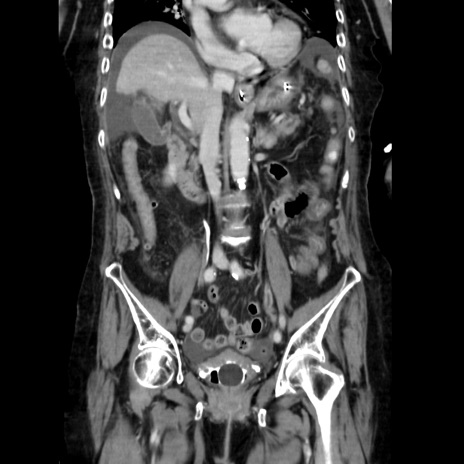

症例40(冠状断像)

【症例】90歳代女性

【主訴】腹痛・嘔吐

【現病歴】 食欲低下、嘔吐があり昨日他院受診。肺炎と診断され入院となる。入院後より腹部全体に圧痛あり。胃管留置され経過みていたが、症状持続するため、

当院転院となる。

【既往歴】胸椎圧迫骨折、胆石症

【身体所見】腹部:中央に激痛あり、圧痛あり、反跳痛不明

【データ】WBC 17100、CRP 18.82

他院CT

冠状断像